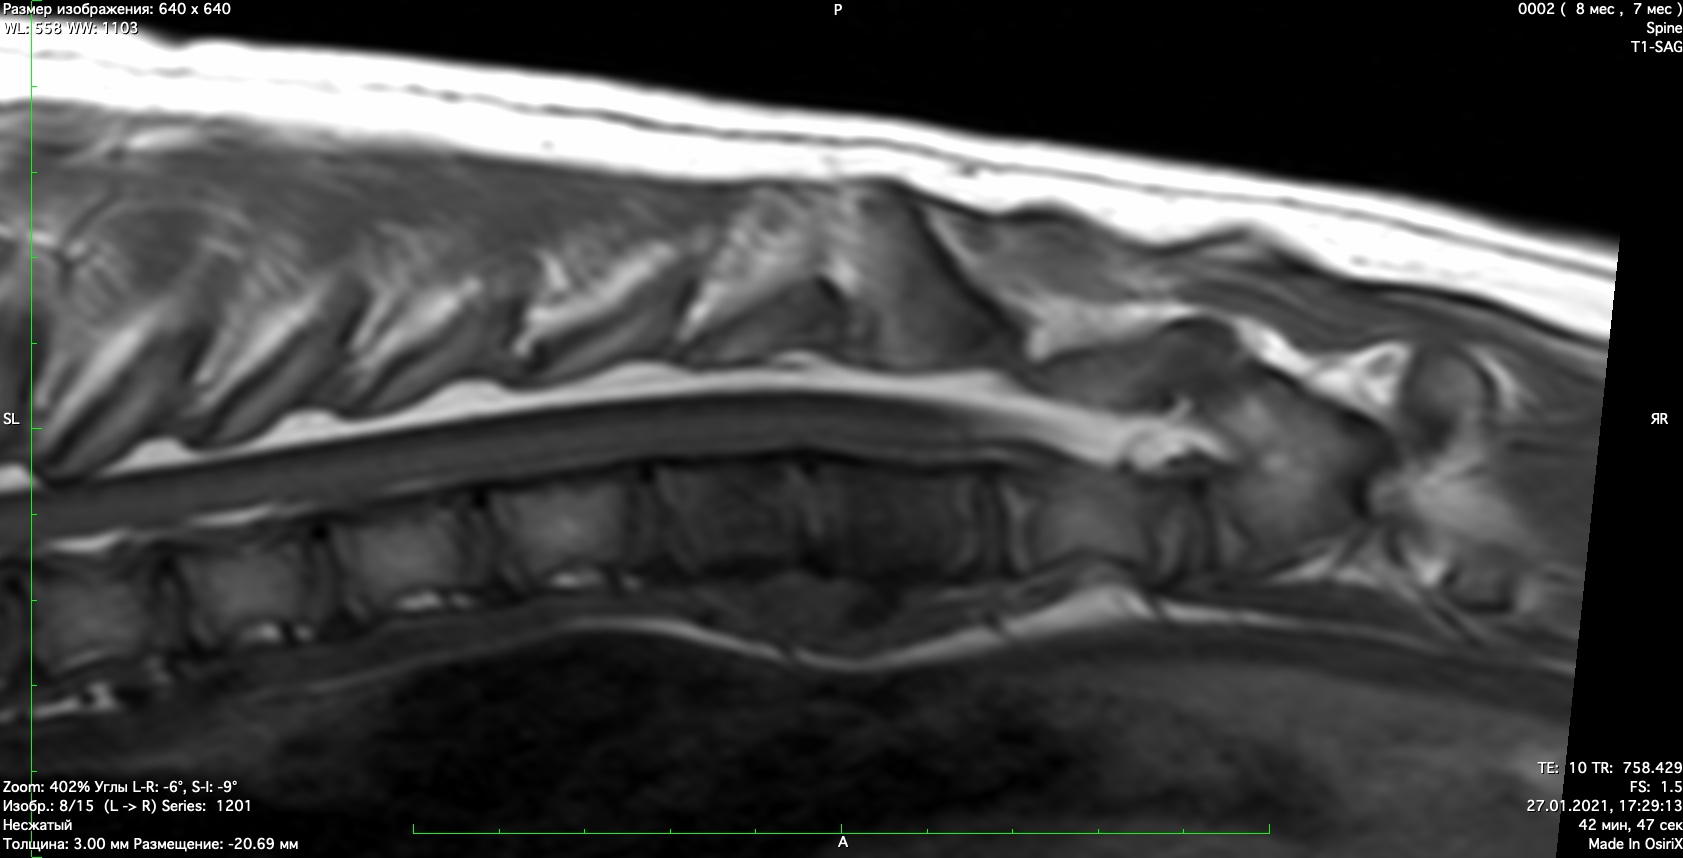

При проведении неврологического осмотра установлено- неврологический дефицит отсутствует, сильная болезненность при пальпации поясничного отдела позвоночника При проведении мрт диагностики установлено признаки воспаления позвонков поставлен диагноз-дискоспондиллит. начато лечение дискоспондиллита -антибиотиками